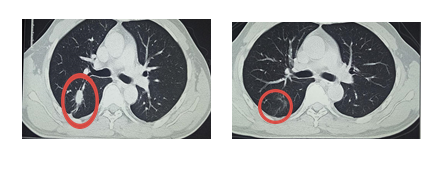

病例一:肺恶性肿瘤